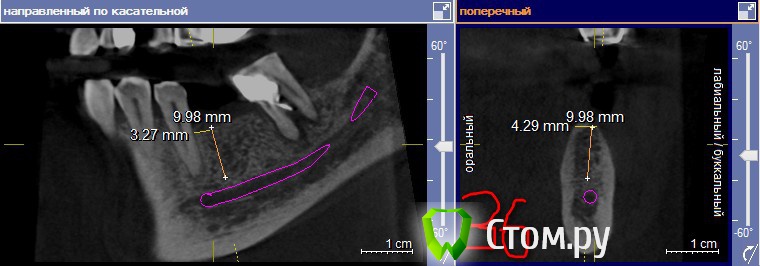

lavrikk Опубликовано 10 мая, 2014 Поделиться Опубликовано 10 мая, 2014 Коллеги, планируется установка имплантантов на Н.Ч. в области 36,37, 46, 4738 удален 10 дней назад, 48 решено сохранять, устраняя наклон ортопедической конструкцией.Смущает толщина гребня-планирую ставить 3.4-10(8) мм Dentium, но платформа у него 3.6.Понимаю необходимость НКР и справа и слева, но ниразу не делал(Вопрос вот в чем, лучше установить импланты в правильные позиции и что будет не в кости засыпать ауто+ксено и мембрана,либо сошлифовать гребень установить более апикально для выигрывания ширины.А также вопрос-как поступаете когда остался небольшой остаток корня в области проекции винта в кости(как на 47), удаляете заранее или во время имплантации аккуратно?Буду благодарен за любую помощь! Ссылка на комментарий

Mane Опубликовано 10 мая, 2014 Поделиться Опубликовано 10 мая, 2014 Можно все таки чуть чуть с экспандерами поиграться. и чуть подраздавить кость.Сделайте ваксап - по нему каппу - и расставьте импланты в нормальном положении. На мой взгляд от оставшихся моляров только вред. На вынос их!Импланты берите 3.6 на 8 или 4х8 1 Ссылка на комментарий

lavrikk Опубликовано 11 мая, 2014 Автор Поделиться Опубликовано 11 мая, 2014 Можно все таки чуть чуть с экспандерами поиграться. и чуть подраздавить кость.Сделайте ваксап - по нему каппу - и расставьте импланты в нормальном положении. На мой взгляд от оставшихся моляров только вред. На вынос их!Импланты берите 3.6 на 8 или 4х8Шаблон сделаю. Набором мисовским вы имеете ввиду разжать кость? Почему на 8мм брать а не на 10 мм ( по причине как раз небольшого заглубления)? И вообще быть готовым к подсыпкам и мембранам? Ссылка на комментарий

mr.Fog Опубликовано 11 мая, 2014 Поделиться Опубликовано 11 мая, 2014 Можно все таки чуть чуть с экспандерами поиграться. и чуть подраздавить кость.Сделайте ваксап - по нему каппу - и расставьте импланты в нормальном положении. На мой взгляд от оставшихся моляров только вред. На вынос их!Импланты берите 3.6 на 8 или 4х8без экспандеров ни куда, а участок уплотнения костной ткани не надо трогать. 48 на выход. Ссылка на комментарий

Mane Опубликовано 11 мая, 2014 Поделиться Опубликовано 11 мая, 2014 Шаблон сделаю. Набором мисовским вы имеете ввиду разжать кость? Почему на 8мм брать а не на 10 мм ( по причине как раз небольшого заглубления)? И вообще быть готовым к подсыпкам и мембранам?можно мисовским можно и другимиимплант длиной 8мм потому как придется заглубить его 1-1,5 мм чтоб избежать костной пластики - 10 мм там не пройдет при такой постановке Ссылка на комментарий

lavrikk Опубликовано 11 мая, 2014 Автор Поделиться Опубликовано 11 мая, 2014 без экспандеров ни куда, а участок уплотнения костной ткани не надо трогать. 48 на выход.А как обойти если там проекция 47? Если б 48 не было, то можно чуть дистальнее... Ссылка на комментарий

faity Опубликовано 11 мая, 2014 Поделиться Опубликовано 11 мая, 2014 А как обойти если там проекция 47? Если б 48 не было, то можно чуть дистальнее...убирайте 4.8 и сможете воткнуть имплант не трогая уплотнение Ссылка на комментарий

reMaToreH Опубликовано 12 мая, 2014 Поделиться Опубликовано 12 мая, 2014 48 на выход. Резорбция кости вертикальная значительная, тем более и в бифуркации. Ссылка на комментарий